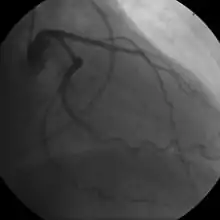

- Coronary angiography

Stable angina is the most common form of ischemic heart disease, and is associated with reduced quality of life and increased mortality. It is caused by epicardial coronary stenosis which results in reduced blood flow and oxygen supply to the myocardium.[71] Stable angina is characterized as short-term chest pain during physical exertion caused by an imbalance between myocardial oxygen supply and metabolic oxygen demand. Various forms of cardiac stress tests may be used to induce both symptoms and detect changes by way of electrocardiography (using an ECG), echocardiography (using ultrasound of the heart) or scintigraphy (using uptake of radionuclide by the heart muscle). If part of the heart seems to receive an insufficient blood supply, coronary angiography may be used to identify stenosis of the coronary arteries and suitability for angioplasty or bypass surgery.[72]